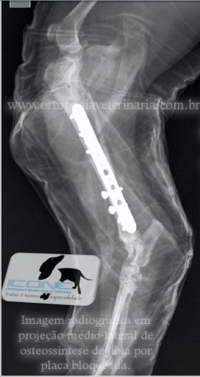

Placa Bloqueada consiste em um novo sistema de fixação interna onde a placa apresenta orifícios duplos, um liso para compressão e outro rosqueado para fixação do parafuso que se fixa a placa. Promove enorme estabilidade a fratura sendo possível associar parafusos neutros e compressivos.